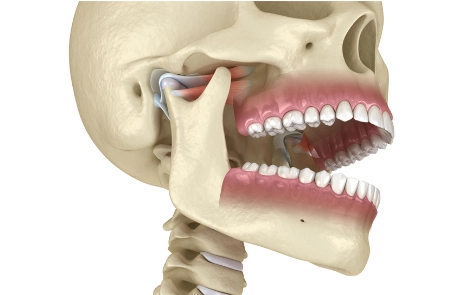

Ursache vieler Probleme ist oftmals der Biss. CMD (Craniomandibuläre Dysfunktion) bezeichnet Störungen im Zusammenspiel von Kiefergelenken, Muskeln und Biss — und bleibt oft unbemerkt.

Wie CMD-Diagnostik funktioniert

Der gesamte Kauapparat wird untersucht, Kieferbewegungen werden beobachtet und die Muskelbereiche sanft abgetastet, um Verspannungen zu erkennen. Die Kopf- und Körperhaltung wird gemessen.

Wir nutzen Kiefertracking und 3D-Bildgebung, um das Zusammenspiel von Gelenken, Zähnen und Muskeln sichtbar zu machen.